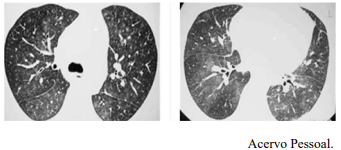

Um Paciente de 25 anos de idade, com tosse e febre de início súbitos 60 dias após transplante de medula óssea, realizou RT-PCR para Covid-19, cujo resultado foi negativo. Constataram-se exame de BAAR negativo, teste de Mantoux negativo e fibrobroncoscopia com cultura e BAAR negativos. A tomografia de tórax apresenta opacidades com atenuação em vidro fosco e pequenos nódulos pulmonares bilaterais, conforme as imagens a seguir.

Considerando esse caso clínico, as imagens apresentadas e os conhecimentos médicos correlatos, julgue o item a seguir.